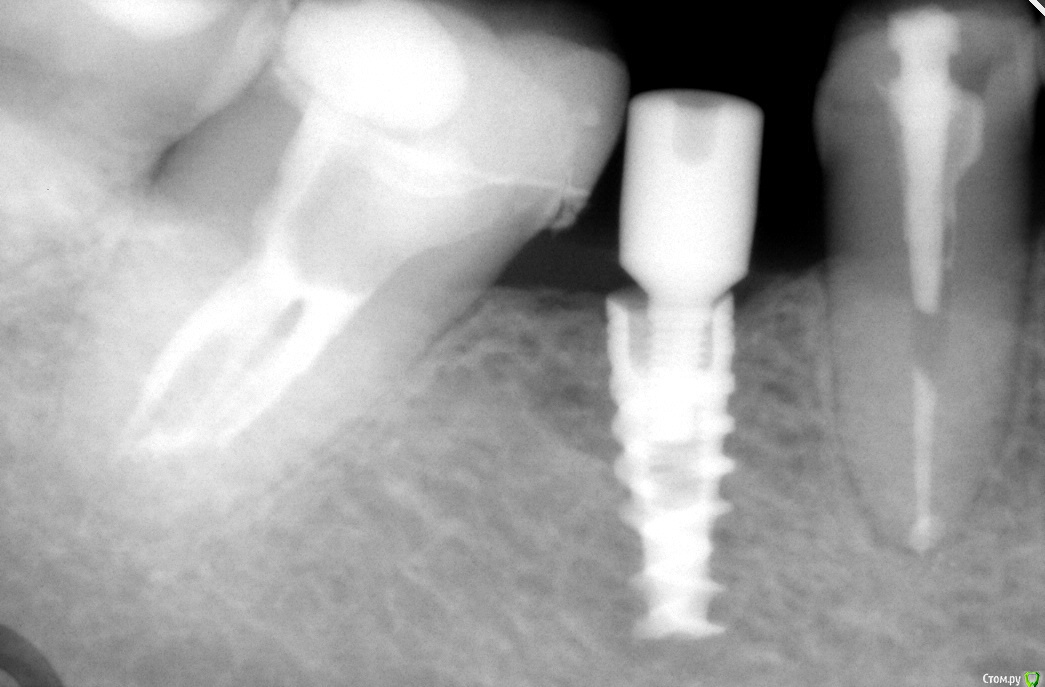

simpsons Опубликовано 16 марта, 2016 Поделиться Опубликовано 16 марта, 2016 Вот такая борода! слезалась резьба внутри импланта! формировалель вкрутил ,но с большим усилием и скрипом метала! у кого какие варианты выхода из этой ситуации? Ссылка на комментарий

Карен Аванесов Опубликовано 16 марта, 2016 Поделиться Опубликовано 16 марта, 2016 Надежный вариант один, выкрутить и поставить новый имплантат. 2 Ссылка на комментарий

simpsons Опубликовано 16 марта, 2016 Автор Поделиться Опубликовано 16 марта, 2016 Жалко выкручивать имплант....интегрировался ведь... Кроме удаления импланта есть предложения? Ссылка на комментарий

Kovalov Igor Опубликовано 16 марта, 2016 Поделиться Опубликовано 16 марта, 2016 это же SPI? у данных имплантов нет набора для нарезания резьбы ? видел такие в каталоге у Дентиум. Ссылка на комментарий

simpsons Опубликовано 16 марта, 2016 Автор Поделиться Опубликовано 16 марта, 2016 это же SPI? у данных имплантов нет набора для нарезания резьбы ? видел такие в каталоге у Дентиум. Вы правы! Ссылка на комментарий

simpsons Опубликовано 16 марта, 2016 Автор Поделиться Опубликовано 16 марта, 2016 Можно туда шикарную вкладку замастырить))слыхал о таком!Резьба слизывается где- на середине резьбы импланта...я думаю,может укоротить винт? Ссылка на комментарий